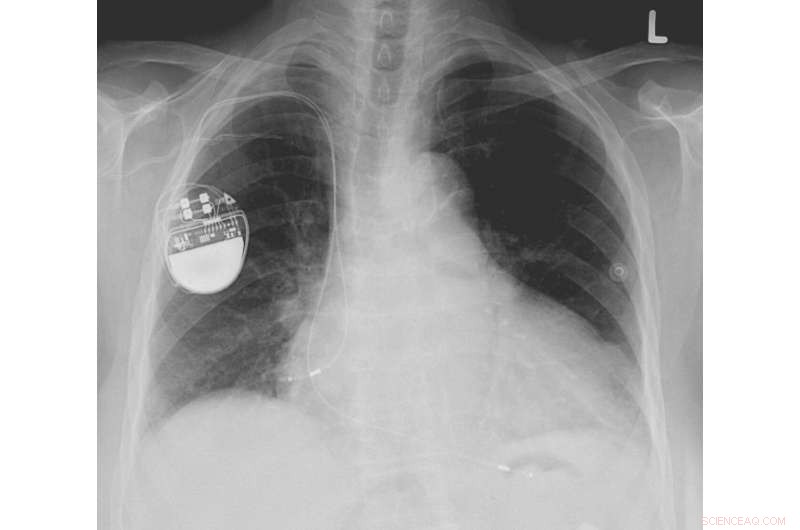

The new material could be used to develop devices that convert blood pressure into a power source for pacemakers. Credit: Image of pacemaker by Lucien Monfils, licensed under the Creative Commons Attribution-Share Alike 3.0 Unported, 2.5 Generic, 2.0 Generic and 1.0 Generic license.

The material's potential biomedical applications include internal biosensors and self-powering biotechnologies, such as devices that convert blood pressure into a power source for pacemakers.